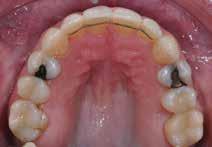

Der ses anterior trangstilling i begge kæber og overerupterede 1+1 og 2,1-1,2, hvilket resulterer i dybt bid med 2- tæt på ganepåbidning. Der er normale sidetandsrelationer, men der ses 5 mm horisontalt overbid (HOB) og 7 mm vertikalt

overbid (VOB). Papillen mellem 1+1 er betydeligt reduceret pga. fæstetab, og de mesialt kippede 1+1 har resulteret i en ”dark triangle”. Den facioorale funktion er for nuværende i.a. Panoramarøntgen (Fig. 1, I) viser marginalt knogletab i begge kæber og fravær af 8,7+7,8 og 8,7-8.

Objektivt anbefales behandling af det dybe bid, som ubehandlet forventes at forværres yderligere over tid. Patienten har ønske om behandling med æstetisk ortodontisk apparatur, alignere, og det vurderes muligt at behandle malokklusionen med alignere. Dog anbefales det generelt, at alignere undgås eller benyttes med væsentlige modifikationer af alignerens retention ved tandmobilitet, da dette ellers kan medføre jiggling, når aligneren tages af og på mange gange dagligt. På den anden side er der nogen evidens for, at alignerbehandling er associeret med bedre renhold og parodontal sundhed sammenlignet med fast apparatur (16).

Der planlægges alignerbehandling af begge kæber med intrusion af 1+1 og 2,1-1,2, nivellering af trangstilling UK med interproksimal reduktion (IPR) (Fig. 2 A, B) og senere IPR OK for reduktion af dark triangles mellem incisiverne efter nivellering. Patienten instrueres i at benytte alignere 20-22 timer/ dag med alignerskift hver 7. dag, og patienten ses hver 3.-8. uge under forløbet. Den første alignerserie består af 16 alignere for nivellering OK/UK og IPR i UK (Fig. 2). Efter denne serie planlægges IPR mellem incisiverne i OK for reduktion af dark triangles (Fig. 3) samt yderligere intrusion af OK og UK-fronten i 12 refinement-alignere. Patienten udviser god kooperation og er meget tilfreds med alignerapparaturet, som er mindre synligt end det faste apparatur (Fig. 4).